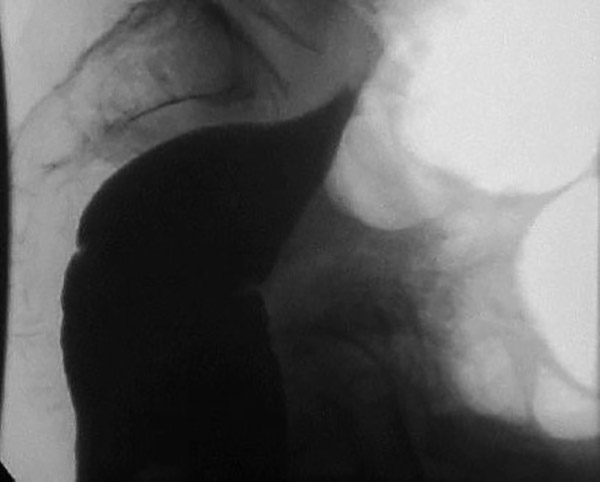

How does sigmoid volvulus occur?

The sigmoid twists on its mesenteric axis, rotating left or right.